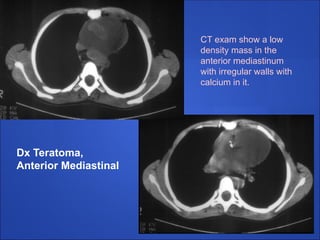

Dx Teratoma,

Anterior Mediastinal

CT exam show a low

density mass in the

anterior mediastinum

with irregular walls with

calcium in it.